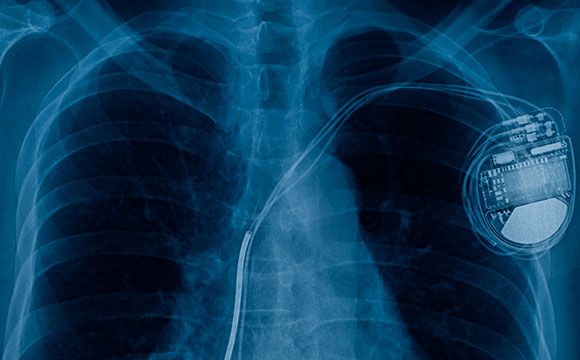

A pacemaker has two main parts. The first part is the wires with electrodes that connect to your heart. These wires continually monitor your heart rhythm. They send the information to the second part of a pacemaker, the pulse generator. The pulse generator is a small battery-operated computer. It recognizes abnormal heart rhythms and responds by sending electrical pulses back to your heart to correct the rhythm.